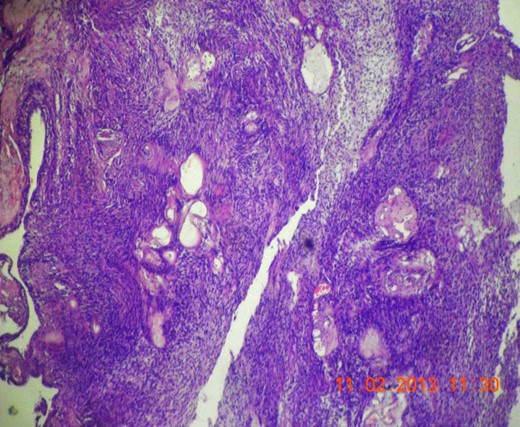

Gross appearance showed 6 × 4 × 4 cm smooth encapsulated right thyroid swelling with a posterior cystic area which was yellowish brown in colour. Walls of the cyst were bright yellow with polypoid areas (Fig. 4). Histology showed classical Antoni A (hypercellular areas) with Verocay bodies and Antoni B (hypocellular) pattern, with interspersed thyroid cells along the periphery (Figs 5–7). The lesion was reported to be arising from within the thyroid gland itself and not extrinsic to it.

Microscopic section (H&E slide, 40×) of well-encapsulated lesion with hyper- (Antoni A) and hypocellular (Antoni B) areas. Multiple cystic areas are also seen.